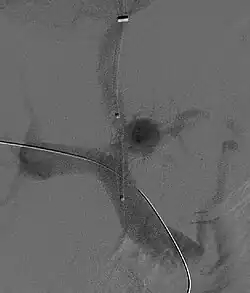

Fluoroscopic image of TIPS in progress. A catheter has been passed into the hepatic vein and after needle puncture, a guidewire was passed into a portal vein branch. The tract was dilated with a balloon, and contrast injected. A self-expandable metallic stent has yet to be placed over the wire.

Once the catheter is in the hepatic vein, a wedge pressure is obtained to calculate the pressure gradient in the liver. Following this, carbon dioxide is injected to locate the portal vein. Then, a special needle known as a Colapinto or Rösch-Uchida is advanced through the liver parenchyma to connect the hepatic vein to the large portal vein, near the center of the liver.[13] The channel for the shunt is next created by inflating an angioplasty balloon within the liver along the tract created by the needle. The shunt is completed by placing a special mesh tube known as a stent or endograft to maintain the tract between the higher-pressure portal vein and the lower-pressure hepatic vein. After the procedure, fluoroscopic images are made to show placement. Pressure in the portal vein and inferior vena cava are often measured as the dynamic changes in the portal pressure system can help predict mortality after TIPS.[11][14]